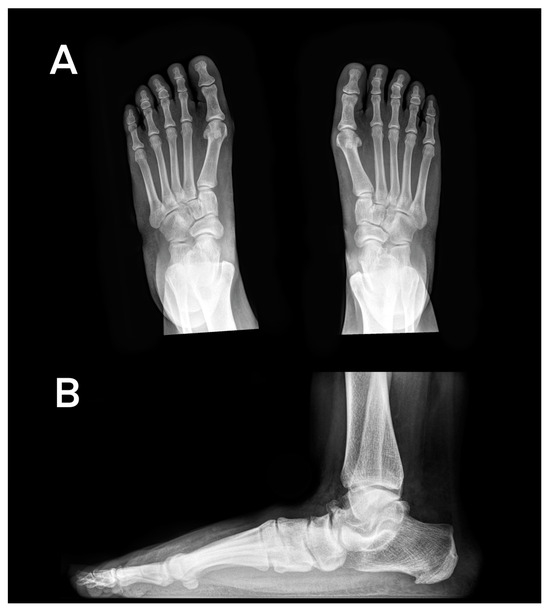

According to the lateral radiographs, the talonavicular (49.0%) and cuneonavicular joints (41.2%) were the most prominent sites of OA, presenting definite osteophytes with mild JSN. The TMT1 (13.7%) and MTP1 joints (7.8%) were less affected by osteophytes and JSN (Figure 1).

Dorsoplantar radiographs revealed TN OA in twenty-two limbs (43.1%); nineteen limbs (37.2%) presented with OA of the CN joint, and seven limbs (13.8%) presented with CC joint. Seven feet (13.8%) presented with TMT1, four feet (7.8%) were affected with MTP1, and five feet (9.8%) presented with Lisfranc OA. The most prominent sites for OA and foot deformities are displayed in Figure 1, Figure 2 and Figure 3.

Figure 2. (A): Weight-bearing, dorsoplantar radiographs of the feet presenting with hallux valgus (HVA > 15°), elevated TCA, and mild JSN of the talonavicular joint. (B): Lateral radiograph of the left foot and ankle presenting with moderate JSN of the TN joint, mild JSN of the CN joint, and a decreased Meary angle and calcaneal inclination angle.